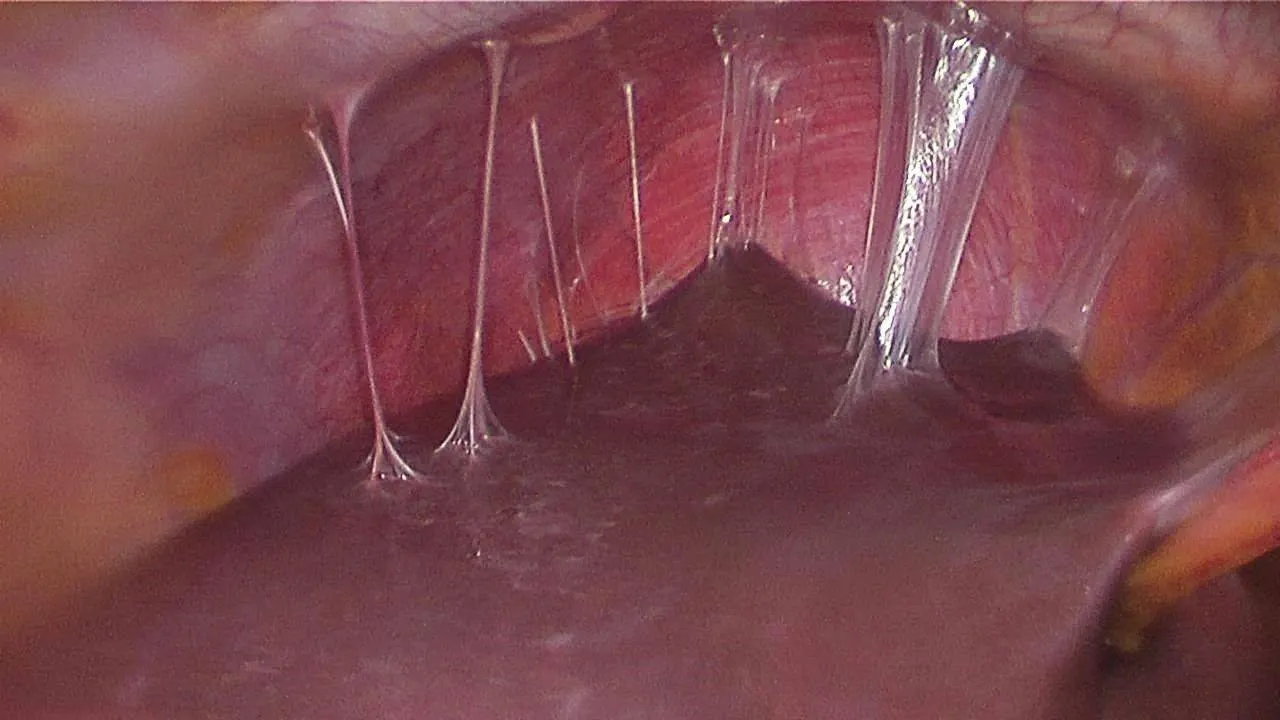

Fıtık onarımının dünya çapında en yaygın cerrahi prosedürlerin başında geldiğine işaret eden Prof. Dr. Esra Karaca, her yıl yaklaşık 20 milyon hastanın fıtık gelişimine bağlı olarak ameliyat edildiğini açıkladı. Karın duvarında oluşan defektin, mesh adı verilen bir tıbbi tekstil materyali implante edilerek onarılmasının da bu alanda yapılan en yaygın cerrahi müdahalelerden birisi olduğunu söyleyen Prof. Dr. Esra Karaca, “Bununla beraber, kullanılan meshler ciddi adezyonlara neden olmaktadır. Daha önce fıtık ameliyatı olmuş hastaların yüzde 90’ından fazlasının ameliyat sonrası adezyon semptomları gösterdiği tespit edilmiştir. Adezyonlar ise kronik karın ağrılarına ve iç organlarda ölümcül tıkanıklıklara yol açabilmektedir. Yeni ürünler denenmesine rağmen, post-operatif adezyon henüz başarıyla önlenememiştir. BUÜ Tıp Fakültesi Hastanesi’nden Türkiye ile ilgili bir projeksiyon yapılarak, ülkemizde bir yılda kullanılan fıtık mesh sayısının 100 bin civarında olduğu sonucuna varılmıştır. Bu nedenle; proje çerçevesinde geliştirilecek başarılı bir kompozit meshin, yurt dışından mesh ithalatını önemli oranda azaltacağı öngörülmektedir” açıklamasında bulundu.

Karaca ayrıca projede, karın fıtıklarının onarımında kullanılmak üzere çörek otu yağı içeren anti-adezyon özellikli nanolifli yüzey ile takviyelendirilmiş PP örme mesh yapıların geliştirilmesi ve kompozit meshlerin fıtık onarımı ve adezyon önleme performansının in vitro ve in vivo çalışmalarıyla değerlendirilmesini hedeflediklerini de sözlerine ekledi.